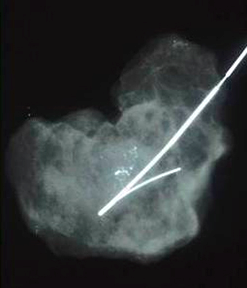

US guided hook wire localization and excision biopsy for impalpable lump

When an impalpable lump is identified under ultrasound image, a hook wire is placed and the lump is excised or biopsied under US guidance.